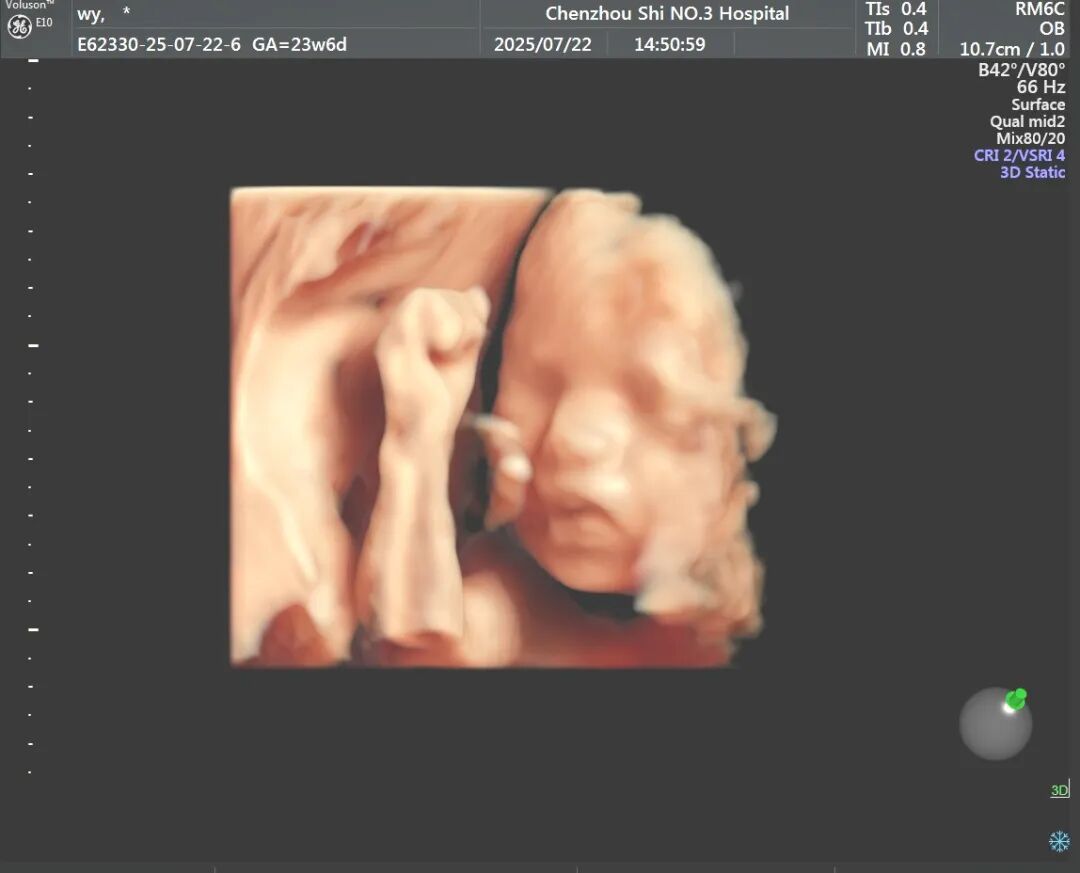

今年7月22日,孕24周的文女士(化名)在我院做四维彩超时,超声中心医生发现胎儿脐带局部堆积、缠绕,凭借专业敏感性和细致操作,医生最终在彩色多普勒图像中识别出一段典型的“环状”交叉结构,而且中心可见连续的血管壁回声。基于这一关键征象,超声团队果断在报告中提示“高度怀疑脐带真结”。